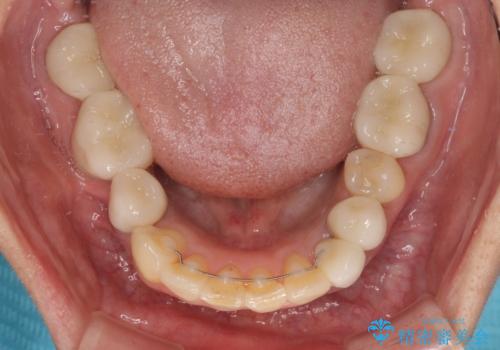

矯正治療によって前歯にスペースを作り、左右対称となるようにオールセラミッククラウンにて補綴治療を行うとしました。

他にも奥歯の咬み合わせに問題があったので、全顎的な矯正治療を行い、前歯以外にも口を開けたときに目立つ奥の銀歯をセラミッククラウンにて補綴治療を行うこととしました。

前歯の横幅が大きいことも気になっていたので、矯正治療で前歯5本の幅をコントロールしながら移動させ、治療開始前より一回りサイズの小さいセラミッククラウンを装着することができました。